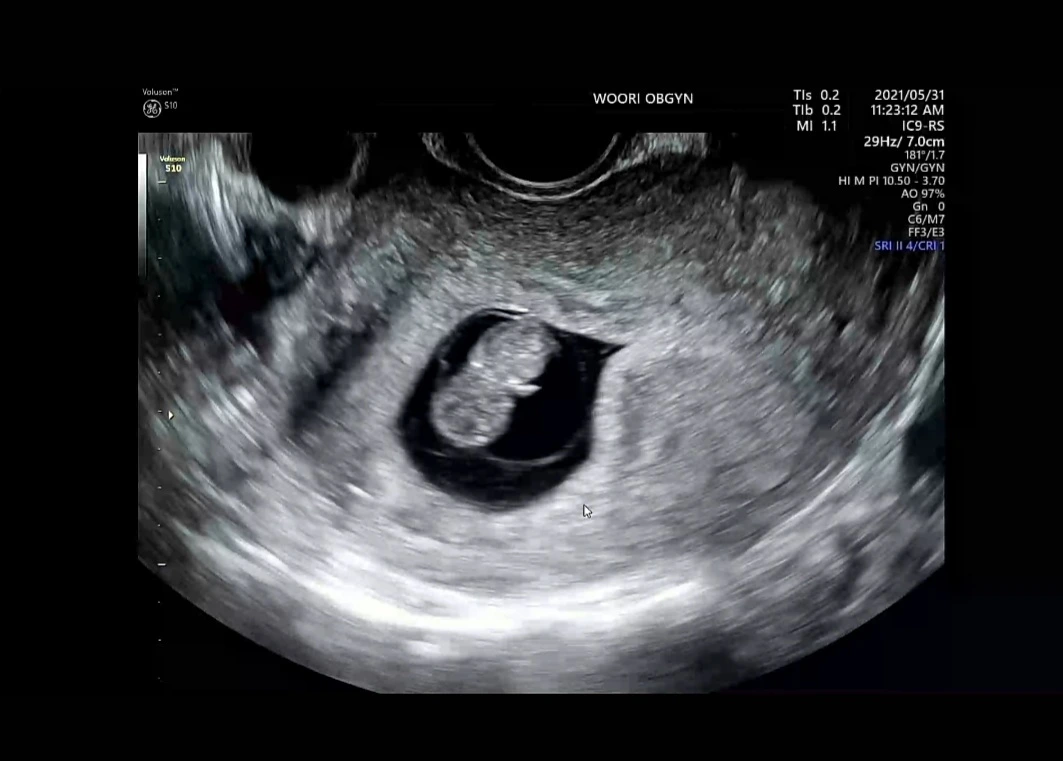

초음파 기계를 통해서 보여진 커다란 TV에서 우리 아가가 보이기 시작했다.

“자, 여기 보시면 우리 아가 잘 크고 있죠? 저번 하고 다르게 아가 형태가 되고 있는 거 같죠?”

“네! 와 너무 신기해요!”

“자, 양수도 괜찮고 아가 집도 너무 괜찮고 자궁에 혹이 하나 보이긴 하지만 그래도 너무 좋아요. 크게 걱정할 건 아닙니다.

주수에 맞춰 아주 잘 크고 있네요. 오늘 예정일 정하는 날이죠? 아가 크기를 확인해보니까……. 22년 1월 5일이네요.”

손과발이 생긴 2등신 우리아가. 귀여워잉